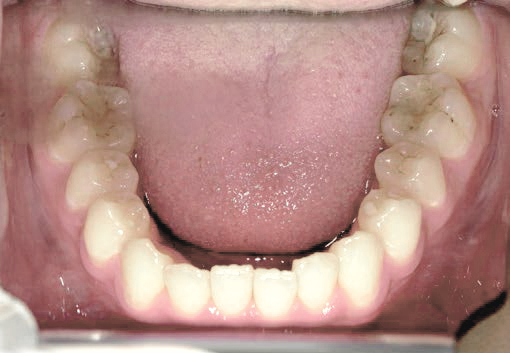

出っ歯

あごや骨格を正しく成長させる矯正治療

Aさん (矯正開始時:8歳)

Before

After

鼻がつまりやすく、口呼吸をしているために上あごが狭い状態でした。また上の前歯がかなり前へ傾いているため、お口をきちんと閉じていることができません。さらに、下の前歯もでこぼこしていました。

治療を終えて

装置によって上あごを拡大し、下あごを少し前へ成長させたことで、永久歯がきれいに並ぶスペースを確保しました。また、お口の機能が向上したことから鼻がよく通るようになり、口呼吸も改善され口も閉じやすくなったので顔の表情もよくなりました。

主訴・治療内容 下あごが後ろに下がり、出っ歯のようになっていることを心配して、無料相談に来院されました。

治療期間 2年半

費用 462,000円(税込)